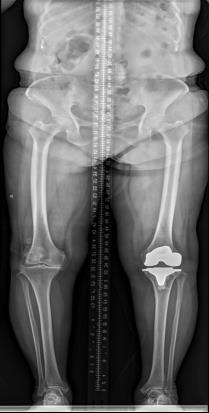

该科擅长对膝关节严重创伤(包括股骨远端骨折、髌骨骨折、胫骨平台骨折等)、膝骨关节炎阶梯化治疗、保膝治疗、膝关节微创单髁置换术、全膝关节置换术、膝关节翻修术具有丰富的临床诊疗经验,追求微创、无痛、快速康复。

对膝关节骨性关节炎采取阶梯化治疗方案,坚持中西并重、内外兼治的原则,取得满意的治疗效果。早期利用中医中药的传统优势,使用中医外治法,例如烫熨治疗、中药涂擦、雷火灸、中药塌渍等,同时辩证内服本院中药制剂及内服方药以及配合西药治疗,开展健康教育,运用运动疗法、物理治疗等辅助支持;中期开展软骨修复、截骨术、单髁置换术、髌股关节置换术等;对于终末期的膝关节OA采用全膝关节置换术。